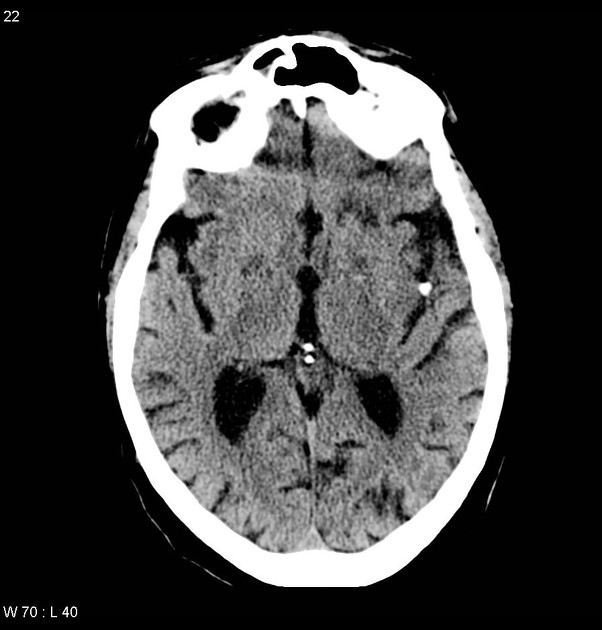

石灰化脳塞栓(calcified cerebral embolism) ・石灰化塞栓子による脳梗塞 ・塞栓源:大動脈弁/僧帽弁石灰化,頸動脈/大動脈弓部等のアテローム性動脈硬化 ・塞栓先:中大脳動脈が最多 ・石灰化塞栓:1-5.5mm,円形-卵円形 ・再発リスクは43-75%と高い(診断と塞栓源指摘は重要) #Rdiag

・石灰化塞栓子による脳梗塞

・塞栓源:大動脈弁/僧帽弁石灰化,頸動脈/大動脈弓部等のアテローム性動脈硬化

・塞栓先:中大脳動脈が最多

・石灰化塞栓:1-5.5mm,円形-卵円形

・再発リスクは43-75%と高い(診断と塞栓源指摘は重要)